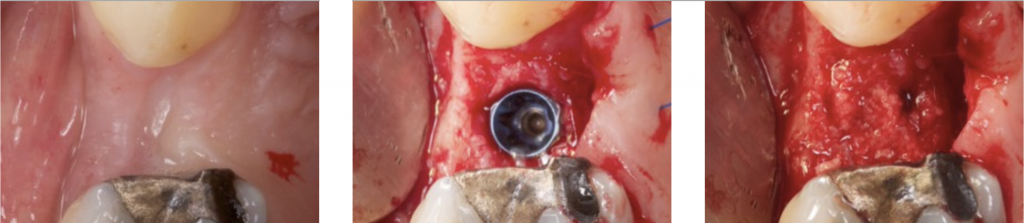

3) DEHISCENCE- TYPE DEFECT: CLASS 2

It is characterized by dehiscence in which the adjacent bone walls provide the volume of the area to be augmented.

Dehiscence of the buccal wall during the implant placement is the most frequent complication.

So, guided bone regeneration of this kind of defect is well documented in the scientific literature (Palmer 1998).

We can say that the regeneration in this kind of defect is very predictable (Kohal 1999).

In posterior and in aesthetically sensitive sites, regeneration with particulate bone substitutes and a resorbable membrane is the treatment of choice. This will provide volume augmentation in the buccal wall.

Some perforations can be performed in the cortical bone to improve bone repair and vascularization of the graft (Rompen 1999).

Particulate bone is applied on the exposed implant surface, and a membrane is shaped and adapted to extend 2 mm beyond the defect margins.